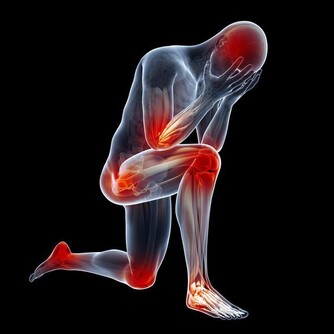

讓我們先來回想一下,靜脈曲張的形成原因主要有哪兩個?一是先天性的血管壁薄弱,這一點我們沒法干預;另外一個原因是久坐久站,姿勢不正確。這個是完全可以改正的。因此,避免靜脈曲張的關鍵就是避免久站久坐。

當你保持站立或者坐立的狀態1小時以上的時候,就應該起身活動一下了,沿著房間慢慢溜達一下,通過小腿的肌肉泵作用,使血液回流;另外,工作了一天,晚上回家躺在床上,我建議大家抬高下肢,這樣也是藉助重力的作用,使下肢的血液回流。

此外,給大家推薦幾個預防靜脈曲張的常見動作。在休息的時候,可以做以下的動作,能很好的預防靜脈血栓的形成。

第一個動作:踮腳尖

踮腳尖的時候,小腿肌肉是緊繃的,這樣會使血液回流。

第二個動作:踩剎車

在坐著的時候,應該怎樣鍛煉小腿肌肉呢?聰明的你肯定想到了解決方法,就是做“踩剎車”的動作,一踩一放,促進血液回流。

第三個動作:空中蹬自行車

在躺著的時候,通過空中蹬自行車的方法也能收縮小腿肌肉,每次至少堅持5分鐘。

以上方法的核心思想就是收縮小腿肌肉,促進血液回流,如果你有其餘的辦法也能達到這種效果,也可以一試。在這裡,主要是給年輕人們提個醒,如果你現在就發現自己有靜脈曲張,一定要加以重視,及時干預,將肺栓塞的可能性降到最低。